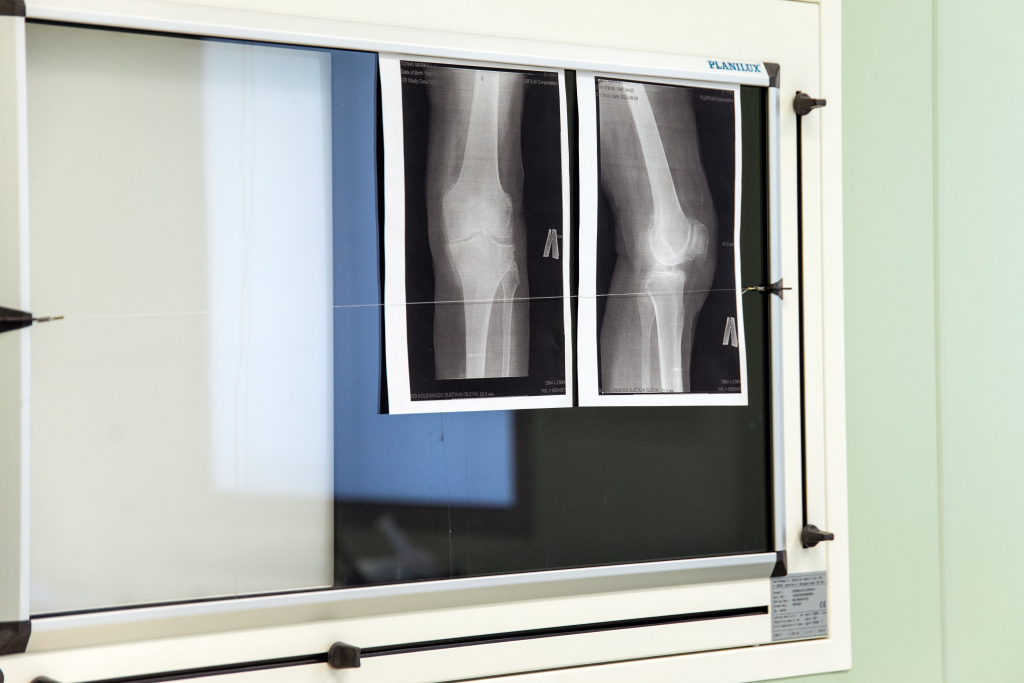

Свыше тысячи взрослых и 330 детей обратились за медпомощью в Сургуте после травм на новогодних каникулах

Сургутская травмбольница сообщает, что самыми опасными являются дорожно-транспортные травмы, и именно их количество в первую неделю нового года вызывает обеспокоенность врачей. Они отмечают, что не обошлось без серьёзных сочетанных травм. За жизнь нескольких пациентов продолжается борьба.

«Всего в период с 1 по 8 января с травмами к нам обратилось 1009 взрослых и 330 детей. В основном преобладал стандартный бытовой и уличный травматизм. Тем не менее, среди госпитализированных пациентов трое – с колотыми ранами, один – с кататравмой после падения с 4 этажа. Помимо травмированных пациентов, наши дежурные бригады спасали и больных с острым нарушением мозгового кровообращения. За это время госпитализировано 11 человек с инсультом», – сообщает пресс-служба медучреждения.